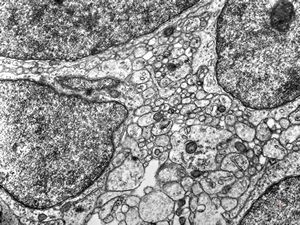

F,50y. | progressive multifocal leukoencephalopathy- viral particles in a glial cell